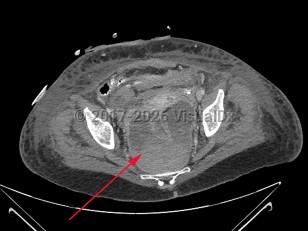

Perirectal abscess

A perirectal abscess is a collection of pus in the perianal area resulting from progression of an infected anal gland.

Perirectal abscesses develop when an anal crypt becomes obstructed, allowing bacterial overgrowth. Complex anorectal abscesses are deeper and classified based on their anatomic location. The American Association for the Surgery of Trauma describes 5 grades of perirectal abscesses: perianal abscess, intersphincteric abscess or ischiorectal abscess, horseshoe abscess, supralevator abscess, and necrotizing soft tissue infection.

The diagnosis is made based on the history and a compatible physical examination. Imaging studies, including computed tomography imaging, may also be helpful.